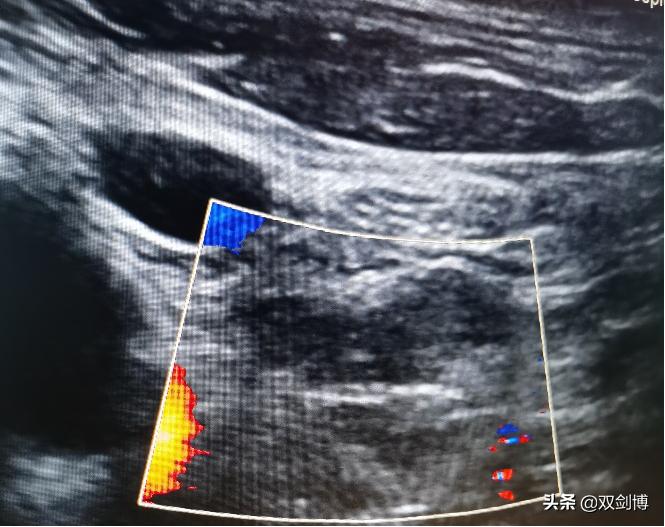

(图示:框内黑色部分为转移淋巴结,半年随访提示淋巴结明显缩小,无血流信号)

近期双剑博医生团队对大量甲状腺癌术后发现颈部淋巴结转移灶消融治疗的病例(无其他器官远处转移),目前随访结果非常满意,患者对无疤无痛的消融过程也是非常满意,期待更多的医疗中心的更大临床数据来进一步说明。